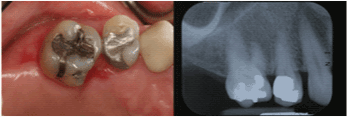

| Mandibular Right Second

Molar |

5 |

52.0% |